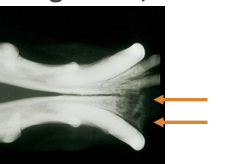

T1: tumor </= 2cm diameter

T2: tumor 2-4cm diameter

T3: tumor >4cm diameter